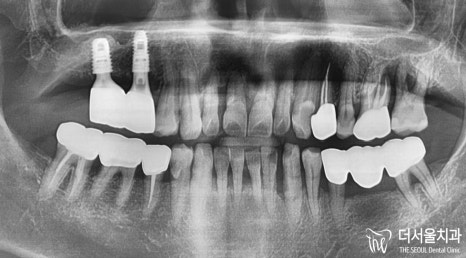

『파노라마(X-Ray) 확인』

잇몸뼈는 얼마나 남아있는지,

상악동과의 거리는 얼마나 되는지

꼼꼼히 확인해줘야 되었는데요.

아무래도 오랜 기간 방치되었는지

골소실이 많이 일어나있네요.

그래서 상악동과의 거리가

가깝다는 것을 확인할 수 있습니다.

결국 뼈이식 임플란트를 진행할 수밖에 없는데요.

# 15는 뼈이식을 할 필요없었으나,

# 16은 상악동 막을 뚫기 때문에

꼭 뼈재료를 넣어 기반을 만들어드려야 되었습니다.

게다가 픽스처 끄트머리가

조금씩 튀어나오기 때문에

이를 가려드리려면,

뼈를 더욱 튼튼히 만들어줘야 되었죠.

이렇게 임플란트 뼈이식을 통하여

뼈재료가 심어진 것을 볼 수 있으며,

상악동 또한 위로 올라가있는 것을

확인할 수 있습니다.

최소 절개를 통하여 실행되었기에

부담이 덜 가게 되었습니다.